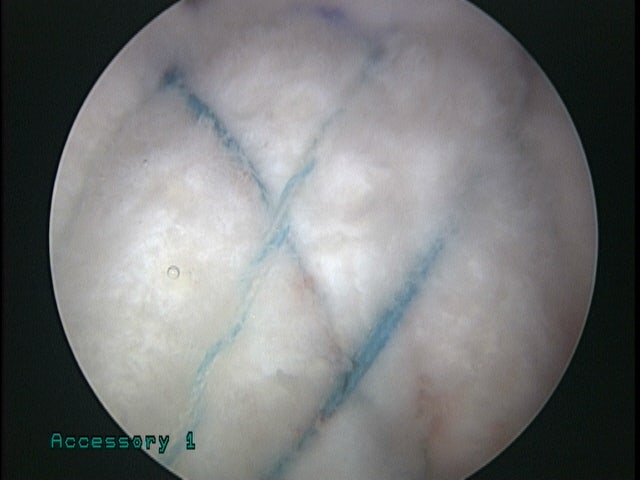

극상근이 아주 얇은 종이처럼 매우 약화된 것이 관찰되었습니다. 단순 봉합만으로는 인대의 강도를 얻을 수 없을 것으로 판단되어 hybride 봉합법을 이용하여 이중으로 인대를 봉합하였고 이두장건과 인조인대(메가덤)을 이용하여 추가적인 보강술을 시행하였습니다.

매우 단단하게 봉합이 잘 이루어 진 것이 확인됩니다. 수술 후 어느정도 시간이 경과되고 다시 MRI 검사를 시행하여 상태를 확인하였습니다.